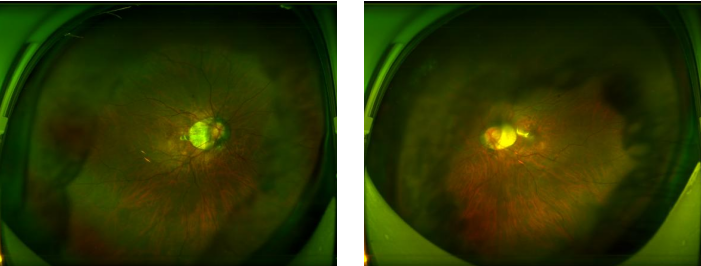

图:容阿姨术前(左)术后(右)眼底广角照相图

术后,容阿姨严格遵医嘱定期复查。12月8日,她再次专程从香港赶到深圳华厦眼科医院。复查结果令人惊喜,她的矫正视力不仅保住了0.8,还提升至 1.0,已经保持1年了!重新拥有了清晰正常的视界。